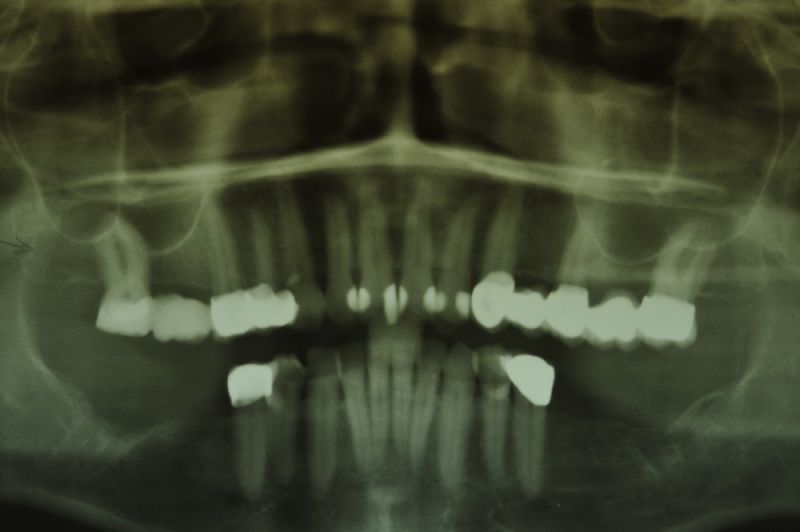

1. Notwendigkeit einer implantatgestützten Kronenversorgung mit der Vorgeschichte, dass die Patientin eine Vielzahl von Behandlern aufgesucht hatte, die eine Implantation im Unterkiefer als nicht durchführbar einschätzten.

2. Extrem schlechte knöcherne Verhältnisse im Unterkieferseitenzahnbereich, die sich intraoperativ noch einmal als ungünstiger darstellten, als bereits in den Voruntersuchungen erkennbar.

3. Sehr dünne Implantate, die von ursprünglich zwei je Kieferhälfte auf letztendlich drei je Kieferhälfte umgeplant werden mussten.